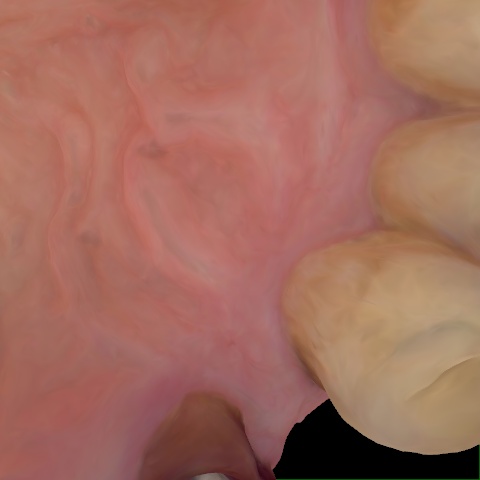

Annotated as "Good"